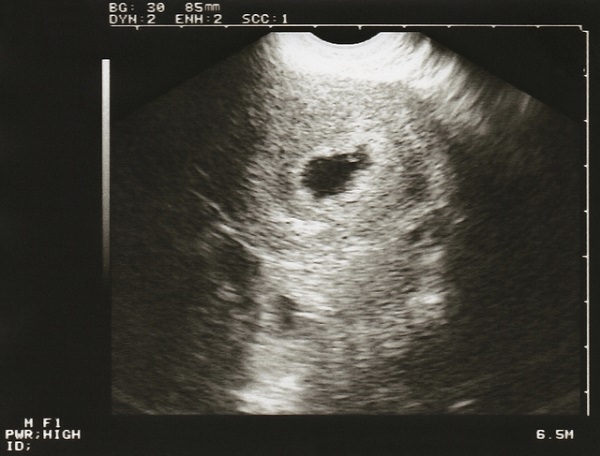

胎嚢とは赤ちゃんを包む袋のようなもので、だいたい妊娠4週から5週目にかけて、確認できることが多いです。

胎嚢が確認できると、まず子宮外妊娠でないことがわかります。この頃の胎嚢の大きさは、10mm前後。病院では胎嚢の大きさをGSということもあります。